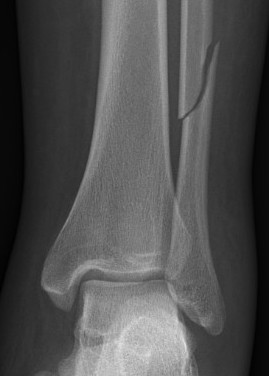

Isolated Weber C fracture

Weber C fracture Weber C fracture with deltoid ligament injury

Maisonneuve injury: proximal fibula with open medial clear space

Definition

Fracture above syndesmosis

Syndesmosis disrupted +/- deltoid ligament